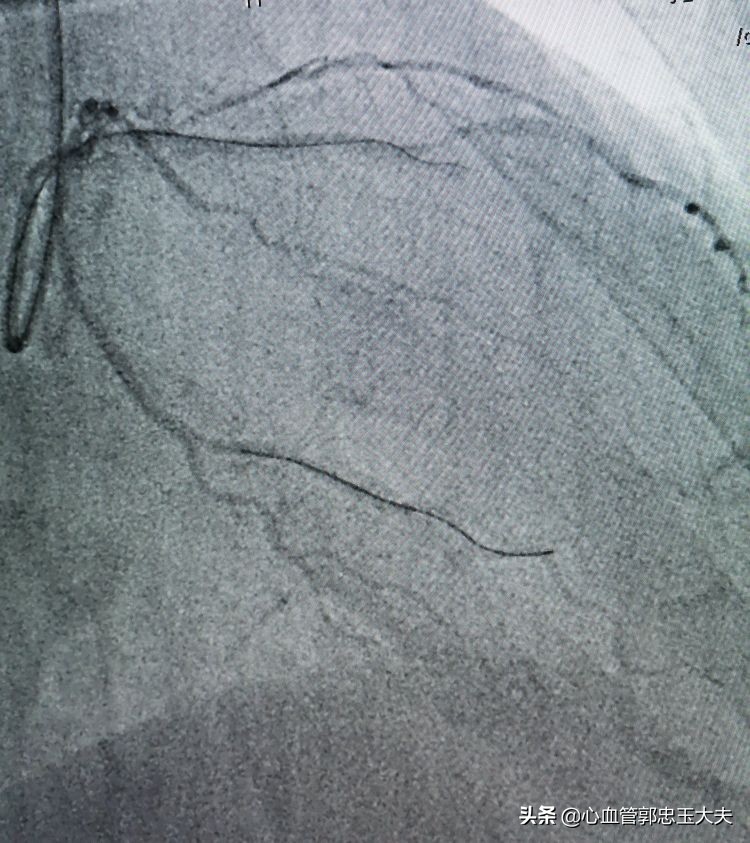

手术策略:计划先开通前降支中远段闭塞段,术*考前**虑到中远段完全闭塞合并钙化,因此开通难度特别大,也跟家属做了充分沟通。EBU大腔到位,回旋支BMW导丝到位加强支撑。FielderXT及Pilot50及150通过困难,反复尝试,FielderXT终于通过闭塞段。如下图

1.5*15mm微球囊通过病变血管困难,在回旋支预埋球囊,扩张加强支撑,微球囊仍然难以通过闭塞病变(如下图)